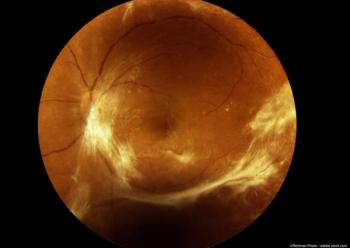

Diabetic Macular Edema